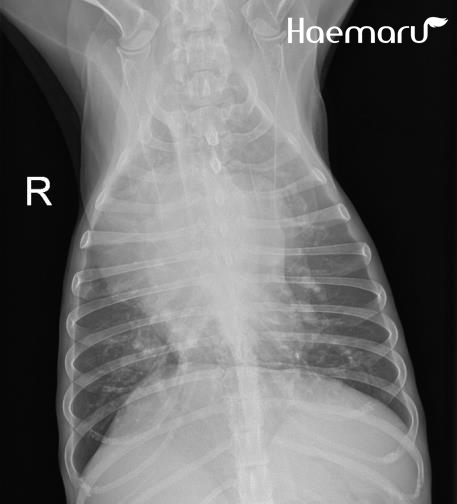

검사상 심장사상충 감염이 확인되어 사상충에 의한 폐고혈압과 우심부전, 이로 인한 흉수 및 복수 발생이 의심되는 상황이었습니다.

마이크로filaria, 우심내 심장사상충, 방사선상의 흉수 소견

입원 처치 후 폐야 개선 소견 확인